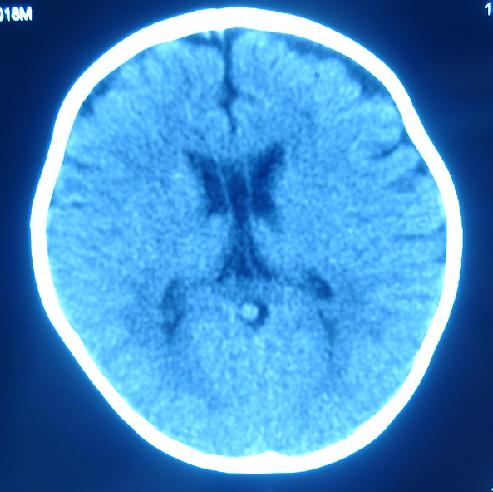

箭头指的地方是占位还是正常的直窦或正常组织?急!谢谢各位老师。

1)箭头所指:galen静脉(即大脑大静脉)。2)透明隔间腔与vergae腔并存。

1)箭头所指:galen静脉(即大脑大静脉)。2)第五脑室、第六脑室。